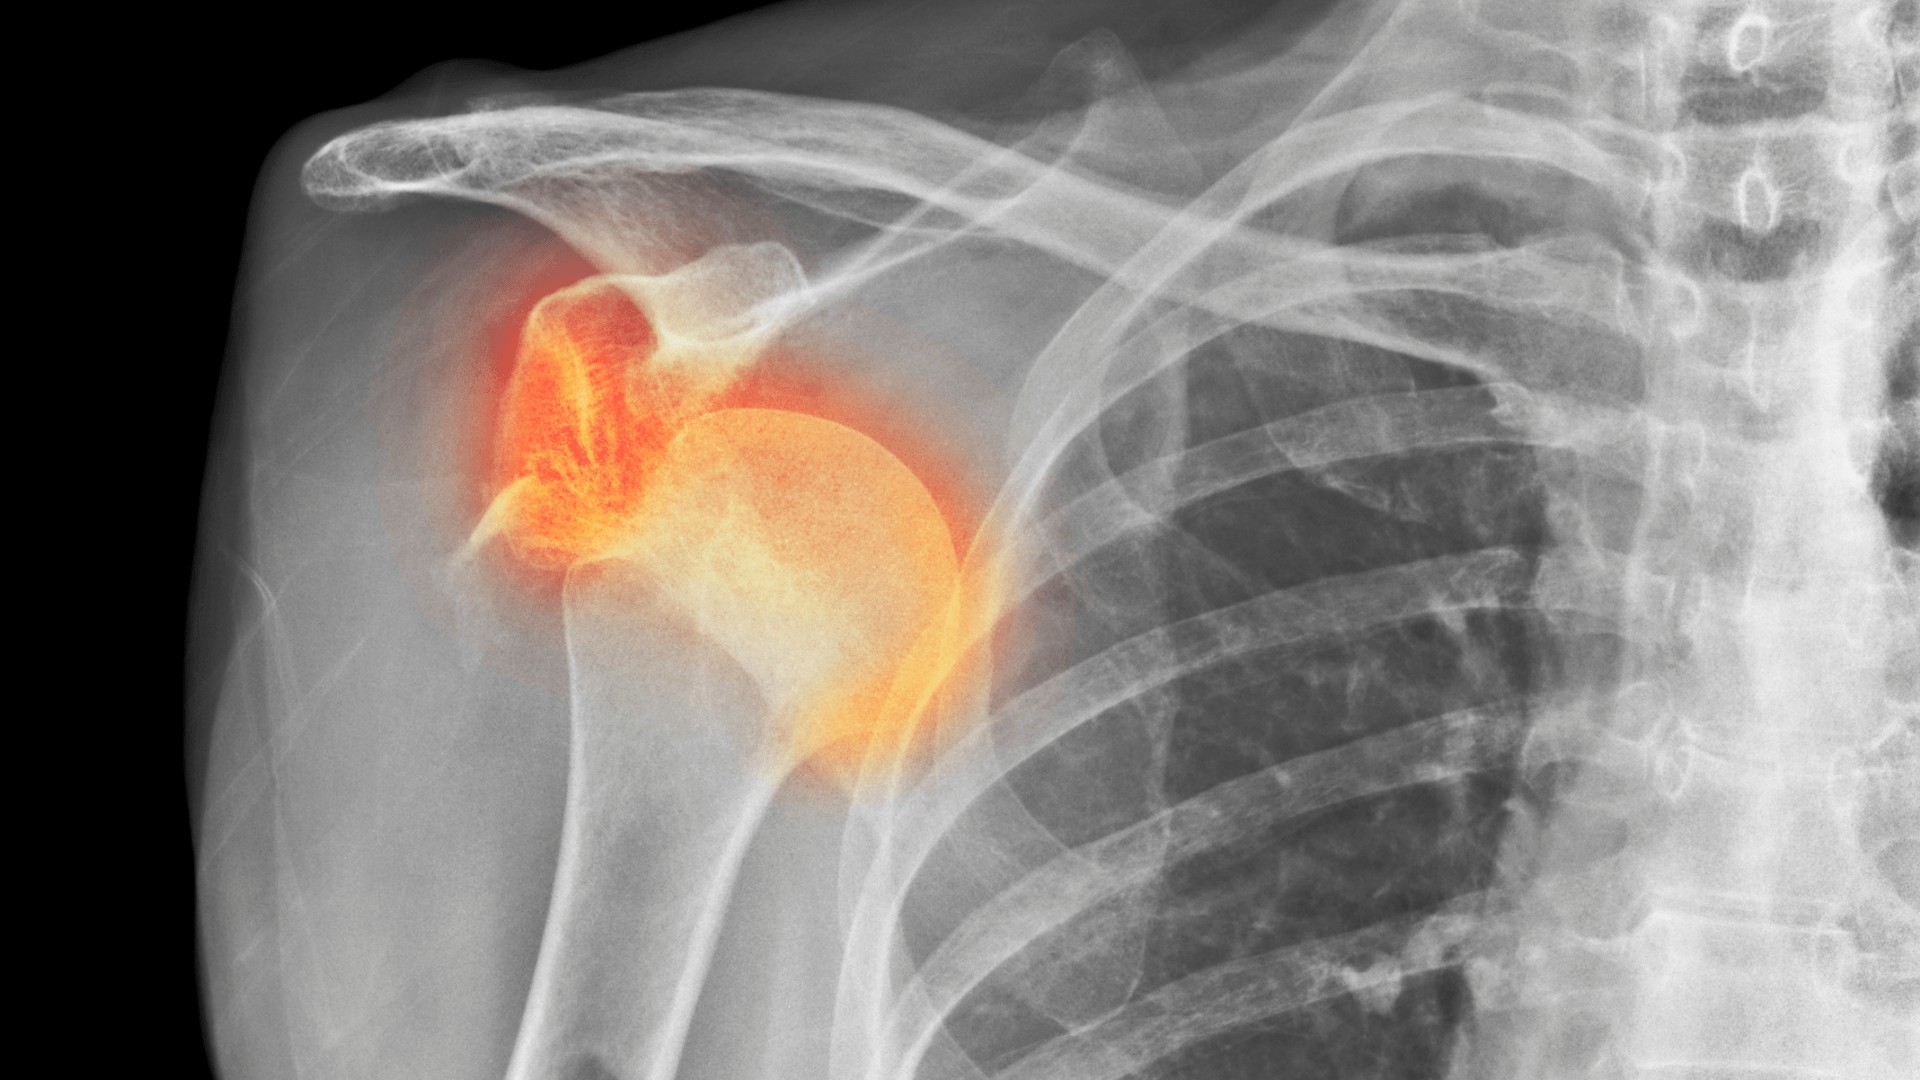

Mängel der MRT-Untersuchung

GIBT EINE MRT-UNTERSUCHTUNG EINDEUTIG WIEDER, WAS SCHMERZEN VERURSACHT?